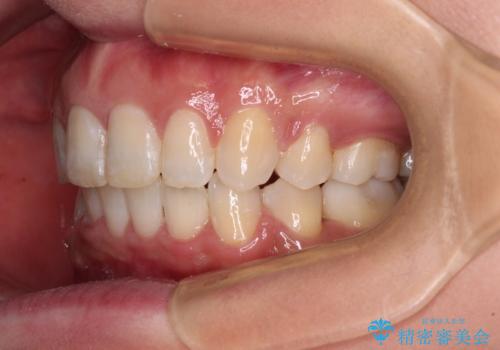

- 上の前歯の飛び出した感じと上下前歯のデコボコを気にして来院された患者様です。

叢生が強く、口元の突出感もあるため、上顎左右第一小臼歯4本を抜歯することとしました。

奥歯の咬み合わせ改善が必要なため、ワイヤー装置による矯正治療を強くお勧めしまたが、本人の希望でインビザラインにて治療を開始することとなりました。